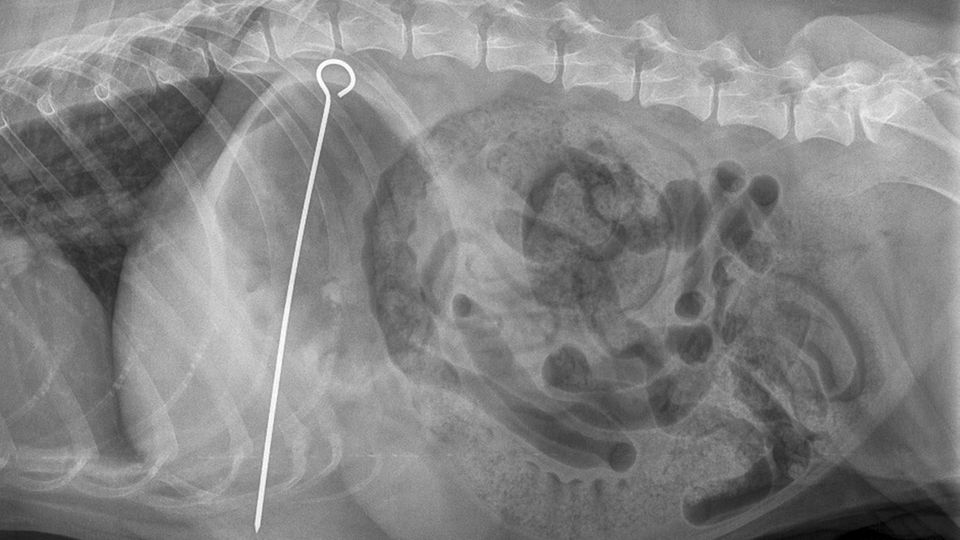

Lebensgefährlicher Snack: Britische Tierärzte haben einem Hund einen 20 Zentimeter langen Kebab-Spieß aus dem Magen operiert. Zuvor hatten sich Ärzte und Besitzer über ein merkwürdiges "Geschwulst" am Bauch gewundert.

Der Shar-Pei, eine Rasse aus China, hatte plötzlich ein merkwürdiges Geschwulst an der Seite. Besorgt brachte seine Besitezrin "Hoshi" daraufhin in die Tierklinik. Was die Tierärzte aus Glasgow auf einer Röntgenaufnahme entdeckten, machte sie dann allerdings fassungslos.

Im Magen des großen Hundes befand sich ein 20 Zentimeter langer Kebab-Spieß aus Metall. Das Tier hatte ihn wohl bei einer Grillparty verschluckt. Nicht selten fressen Hunde versehentlich Steine oder kleine Plüschtiere, aber so ein langer Spieß sei nun doch ungewöhnlich, berichtete Veterinär Ross Allan der Nachrichtenagentur PA.